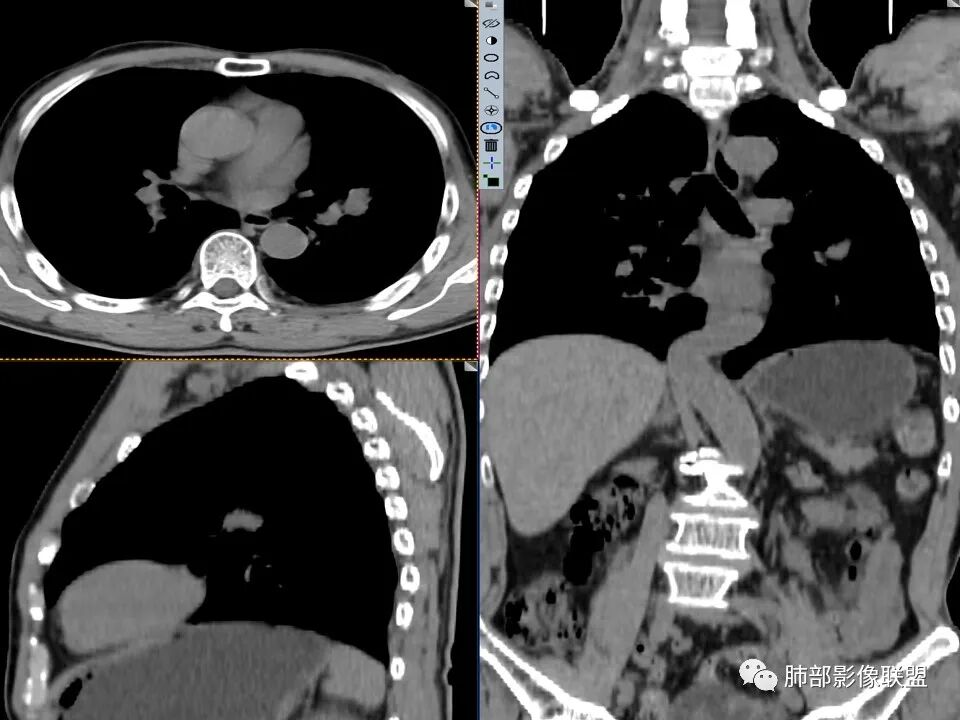

左肺上叶舌段近肺门区不规则结节,密度较均匀,结节边缘平直为主,可见粗短毛刺、毛刺偏软,浅分叶,收缩力不强,膨隆也不明显,周围可见模糊GGO,病灶内部支气管显示不清,病变远端支气管明显扩张,病灶与叶间裂呈宽基底相连,见刀切征,并见叶间裂多发结节影,叶间裂未见明显移位。

患者推测中老年人,无明显临床症状,肺气肿背景不明显,虽然病灶整体炎性征象较多,叶间胸膜多发结节,常规要考虑结核和腺癌,PET-CT肿瘤和炎性病变都可以高摄取,敏感性高,但特异性不高,而且腺癌周围缺乏清晰的磨玻璃及收缩力不强,故暂不考虑;虽然左肺上叶舌段病灶与支气管关系密切,如果周围磨玻璃推测为早期的阻塞性炎症,还有CYFR轻度升高,鳞癌不能除外,但是病灶的整体形态比较符合炎性改变。本病例可惜未行CT增强扫描,无法观察结节的强化特点及病灶内血管走行情况。